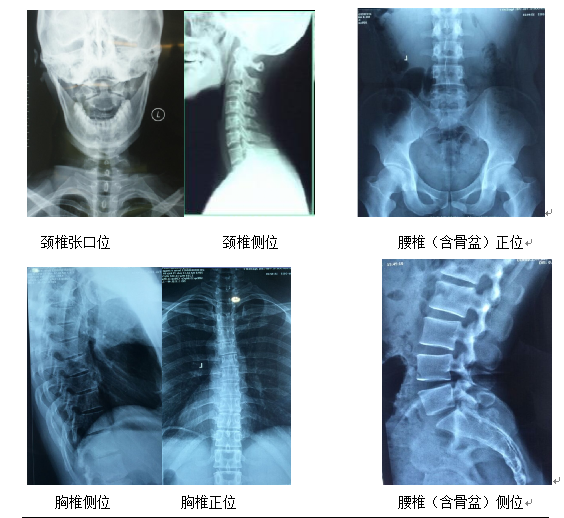

均需要拍摄完整的脊椎图像,包括颈椎张口位,颈椎侧位,胸椎